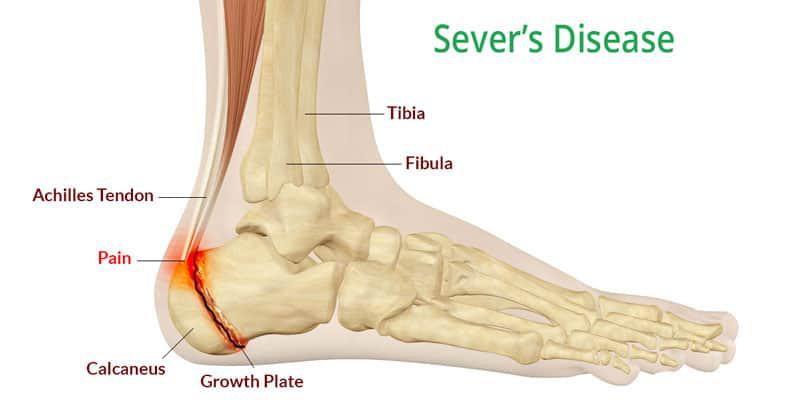

Οι άκροι πόδες (και τα χέρια), αναπτύσσονται πρώτα σε ηλικία 9 – 12 ετών με εμφάνιση συμπτωματολογίας από τα πόδια κυρίως (γιατί τα χέρια δεν επιβαρύνονται το ίδιο), με άλγη στις πτέρνες – σύνδρομο Sever – λόγω της τάσης του Αχιλλείου στην πτερνιαία επίφυση.